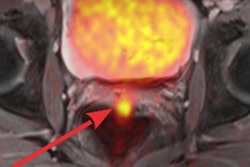

Combining fluciclovine-PET and multiparametric MRI potentially can better detect and classify high-risk prostate cancer than the two modalities alone, according to a Norwegian study. The key to the hybrid modality's efficacy also involves incorporating T2-weighted MRI and diffusion-weighted MR imaging to advance the ability to distinguish between malignant and benign tissue and high-grade tumors from other tissue.